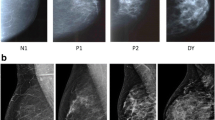

The variability in the patterns and amounts of dense tissue portrayed on the mammogram has been characterized by qualitative measures. The Wolfe scale qualitatively assesses breast density by classifying images into one of four patterns (N1 [fatty], P1, P2 [areas of increasing ductal prominence], and DY [significant densities or dysplasia]) on the basis of quantity and distribution of breast density [21]. The BI-RADS density qualitative assessment is similar to the Wolfe scale in that it incorporates the quantity, distribution, and texture of breast density. New automated commercial technologies are available to quantify breast density volume using methods such as VolparaTM and QuantraTM. Texture features or parenchymal complexity has been evaluated on film-screen mammography examinations and shown to be independent of percentage breast density and relative amounts of fibroglandular tissue [22, 23]. Winkel et al. [22] showed that the discriminatory accuracy was highest when a combination of three methods of assessing relative amounts of density and texture on film-screen mammography examinations were combined. Automated evaluation of textural features or parenchymal complexity of breast density is under investigation for digital images, with researchers in several studies reporting features as independent predictors of breast cancer risk [24,25,26]. Our results extend the literature by showing that an automated quantitative breast density measure (dense breast volume) available in clinical practice combined with a qualitative measure that incorporates the quantity, distribution, and texture of breast density (BI-RADS breast density) improves the classification of women with dense breasts at high breast cancer risk.